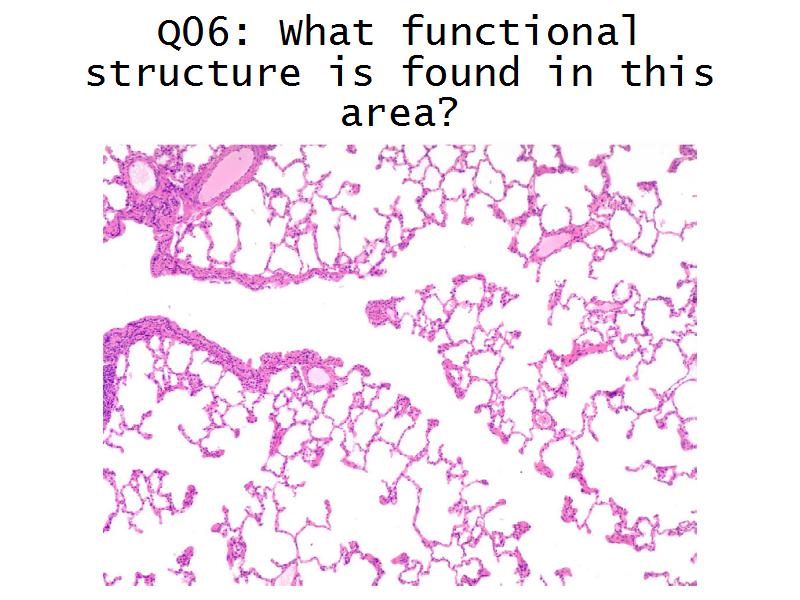

- Basic arrangement of nephrons and collecting tubules in the kidney

- Structure of the nephron and collecting tubules

- Make an annotated diagram of a nephron, including the juxtaglomerular apparatus. Indicate the flow of blood and water in each part, and how solutes are filtered, secreted and reabsorbed.